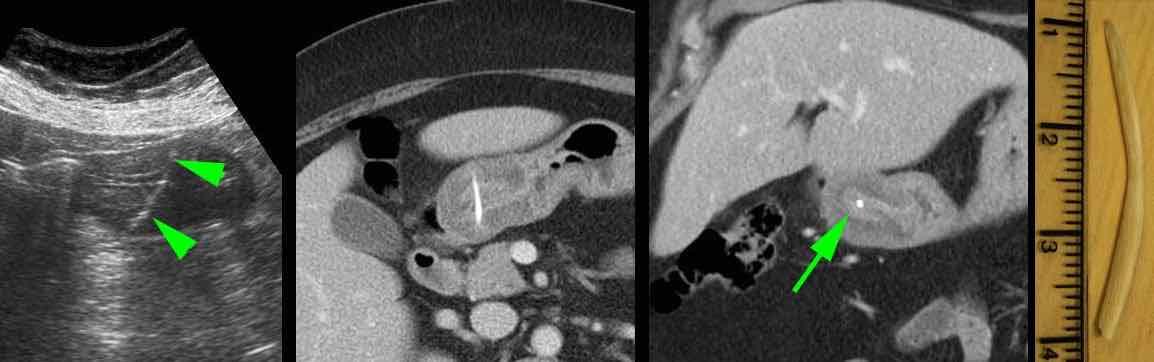

Bệnh nhân nữ 59 tuổi với cơn đau thượng vị không điển hình kéo dài hai ngày.

Siêu âm phát hiện dày thành đáng kể vùng hang vị trước môn vị, trong đó có cấu trúc tăng âm, dạng cong (đầu mũi tên), nghi ngờ xương cá.

CT xác nhận chẩn đoán.

Lưu ý rằng xương cá (mũi tên) có thể dễ dàng bị bỏ sót nếu chỉ xem trên mặt phẳng cắt coronal của CT.

Bệnh nhân hồi phục tốt sau khi lấy dị vật qua nội soi.

Siêu âm và CT cho thấy xương cá xuyên thủng thành dạ dày ngay trước môn vị.

Khi nội soi dạ dày không tìm thấy xương cá, mà chỉ thấy phù nề niêm mạc cục bộ với loét trung tâm (mũi tên).

Việc đưa sâu dụng cụ kẹp lớn vào vùng này cuối cùng đã thành công trong việc gắp được xương cá.